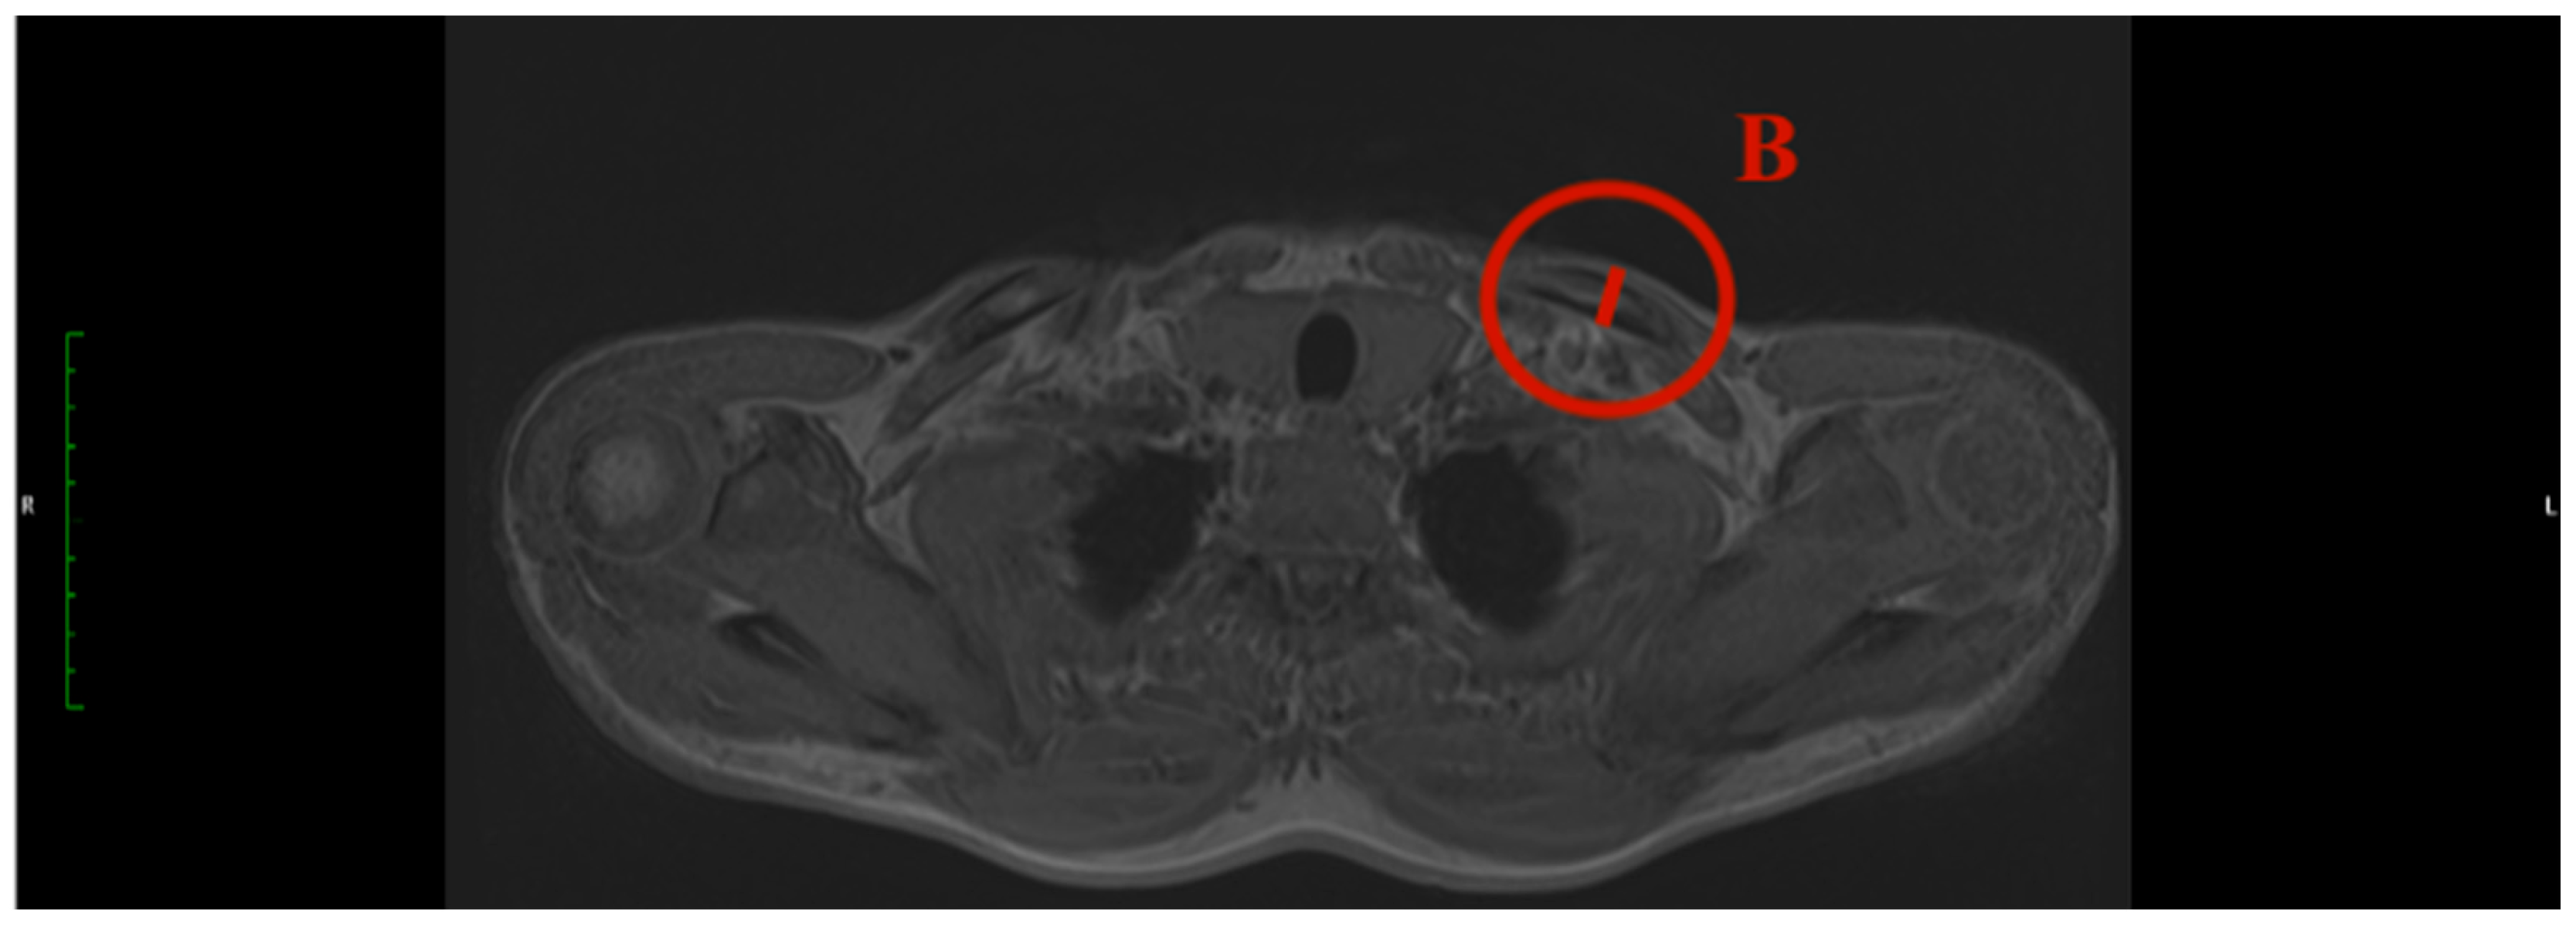

- Clavicular angle: The clavicular angle was measured by the plug-in after two tangents were drawn. One aligns at the articular surface of the clavicular end of the sternoclavicular joint, and the other one at the cranial border of the medial end of the clavicle (Figure 2).